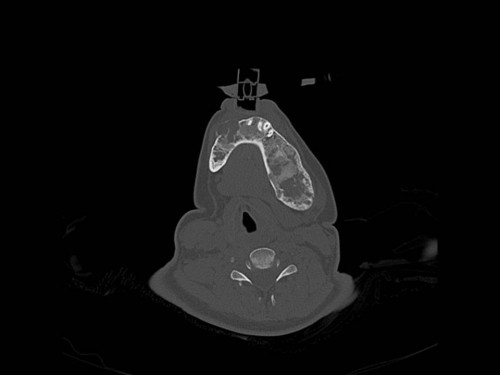

Eine 16-jährige Patientin kommt in eine MKG-chirurgische Praxis zur Abklärung der weiteren Vorgehensweise bzgl. ihrer Erkrankung.

Sie betrachten die angefertigten Röntgenbilder. Welche der folgenden Röntgenbefunde ist korrekt? Ossäre Auftreibungen im Bereich …

- A… der Mandibula links.

- B… des Os frontale links.

- C… des Os zygomaticum links.

- D… des Os temporale links.

- EAlle genannten Aussagen sind korrekt.

Bildgebung - OPAN 2004